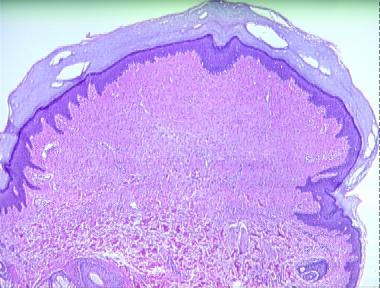

periungual fibroma

Histologic Features